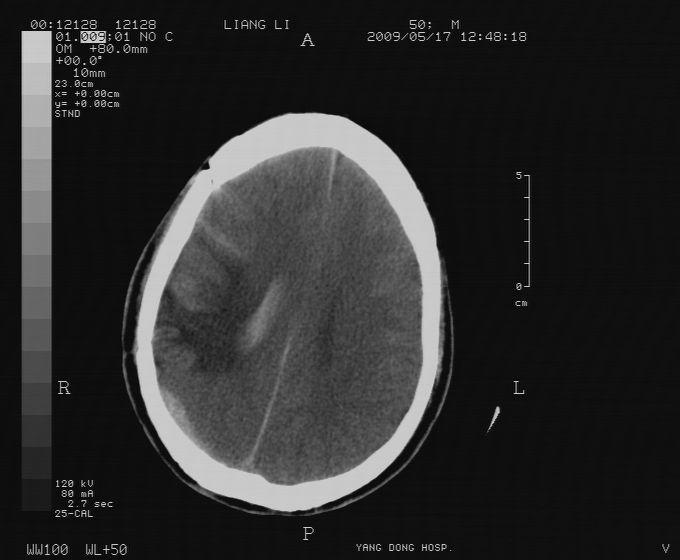

以下是引用zjzjr在2009-5-18 11:26:00的发言:[br]右颞枕叶及基底节区脑出血破入脑室系统,蛛网膜下腔出血,右枕顶部硬膜下血肿.颅骨及颅内低密度软化灶为血肿清除术后改变.

以下是引用随光逐影在2009-5-18 14:47:00的发言:[br]支持 右颞枕叶及基底节区脑出血破入脑室系统;蛛网膜下腔出血;右枕顶部及右侧天幕硬膜下血肿。右侧颅骨术后改变;颅内低密度软化灶为血肿清除术后改变。